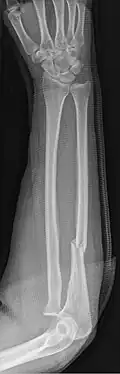

La fractura de Monteggia es una fractura del tercio proximal del cúbito con luxación de la cabeza proximal del radio . Lleva el nombre del cirujano italiano Giovanni Battista Monteggia (1762-1815).[1][2]

El diagnóstico como en todas las fracturas, se basa en la clínica y la radiografía de la estructura anatómica lesionada. La luxación a nivel del codo se puede observar por la gran deformidad e impotencia funcional.

Hay cuatro tipos (dependiendo del desplazamiento de la cabeza radial):[3][4]

- I: Tipo de extensión (60%) el eje del cúbito se angula anteriormente (se extiende) y la cabeza radial se disloca anteriormente.

- II: Tipo de flexión (15%) el eje del cúbito se angula hacia atrás (se flexiona) y la cabeza radial se disloca hacia atrás.

- III: Tipo lateral (20%) el eje del cúbito se angula lateralmente (doblado hacia afuera) y la cabeza radial se disloca hacia un lado.

- IV: Tipo combinado (5%) la diáfisis del cúbito y la diáfisis del radio están fracturadas y la cabeza del radio está dislocada, por lo general en sentido anterior.

Estos se conocen como los tipos Bado